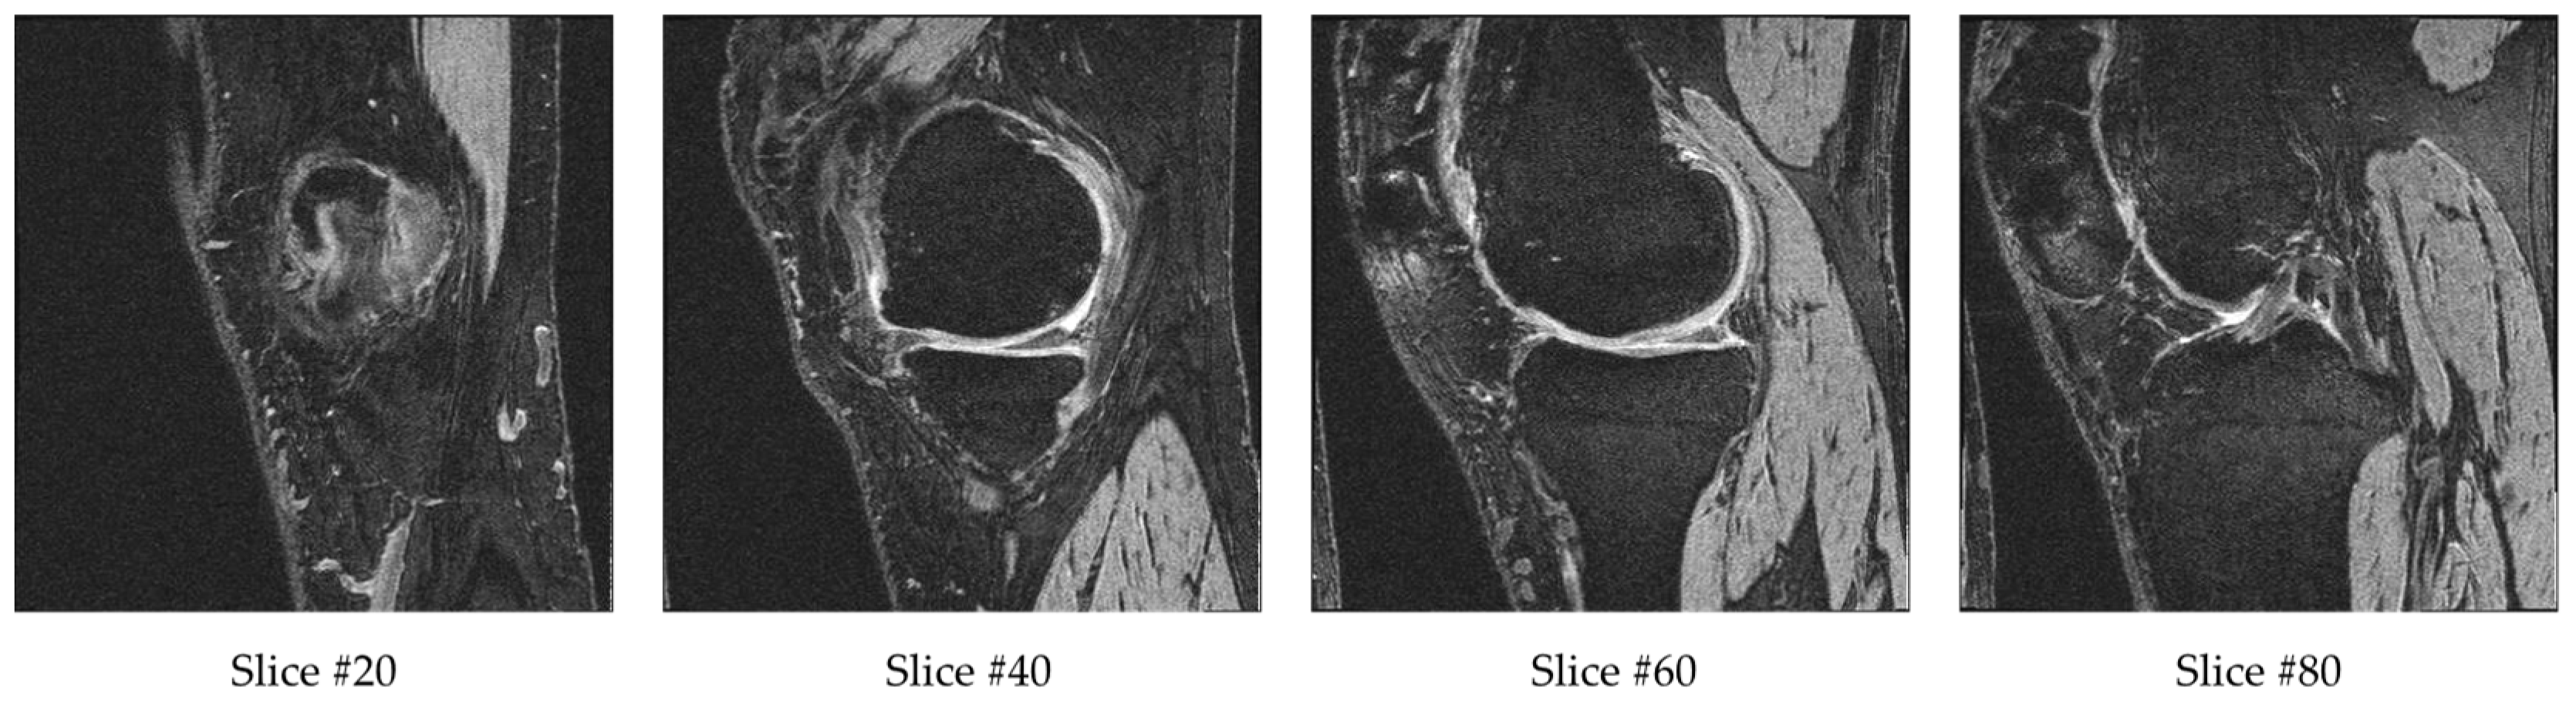

Each sample in the database contains a sequence of 160 MR images. After cropping, the input dimensions of 160 × 160 × 160 were still very high. To further reduce the input data dimensionality, we removed some of the outer and center slices. The reason for removing a few beginning and ending slices is that they do not contain bone or cartilage information. Therefore, they are not likely to contain information related to OA. The reason for removing the middle range slices is that they have ill-defined cartilage regions and blurry bone boundaries due to the transition of medial and lateral bone happening in this range. Example slices are provided in Figure 4. Slice #20 has a small bone region starting, while slice #40 and #60 have larger bones with clearly defined bone boundaries and cartilage. Slice #80 is in the transition range, and therefore the cartilage and bone boundaries are unclear. For each sequence, we excluded the first 10 slices (1–10), middle 20 slices (71–90) and final 10 slices (151–160). The remaining 120 slices (11–70, 91–150) from the 160 slices were fed into the 3D CNN model. This is about 13% of the original 384 × 384 × 160 volume.

Figure 4. A selection of 4 slices from a set of 160 MR images for a single patient’s left knee.